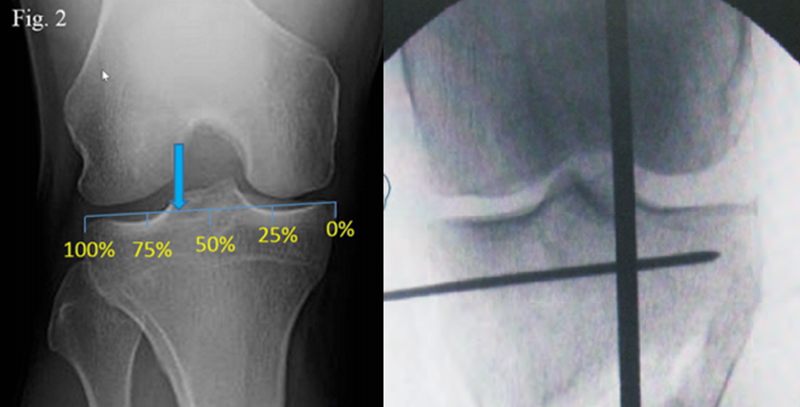

Coventry建议内翻畸形至少矫正至股骨胫骨解剖外翻角8°;Hernigou等发现患者术后机械外翻角在3°-6°时临床效果较好;Fujisawa等发现如果HTO术后力线通过胫骨外侧平台的30%-40%,软骨破坏则不再进展,若通过胫骨平台外侧的62%,则为最佳点,此点被定义为Fujisawa点。

A.双平面截骨,第一刀沿水平面在胫骨后2/3进行截骨,保留外侧合页约10mm,第二刀沿冠状面在胫骨前1/3进行截骨,两刀截骨角度呈110°。B.撑开器逐渐缓慢加大骨缝,注意保留外侧合页。C.力线杆定位,撑开至力线杆经过Fujisawa点。D.进行内固定。